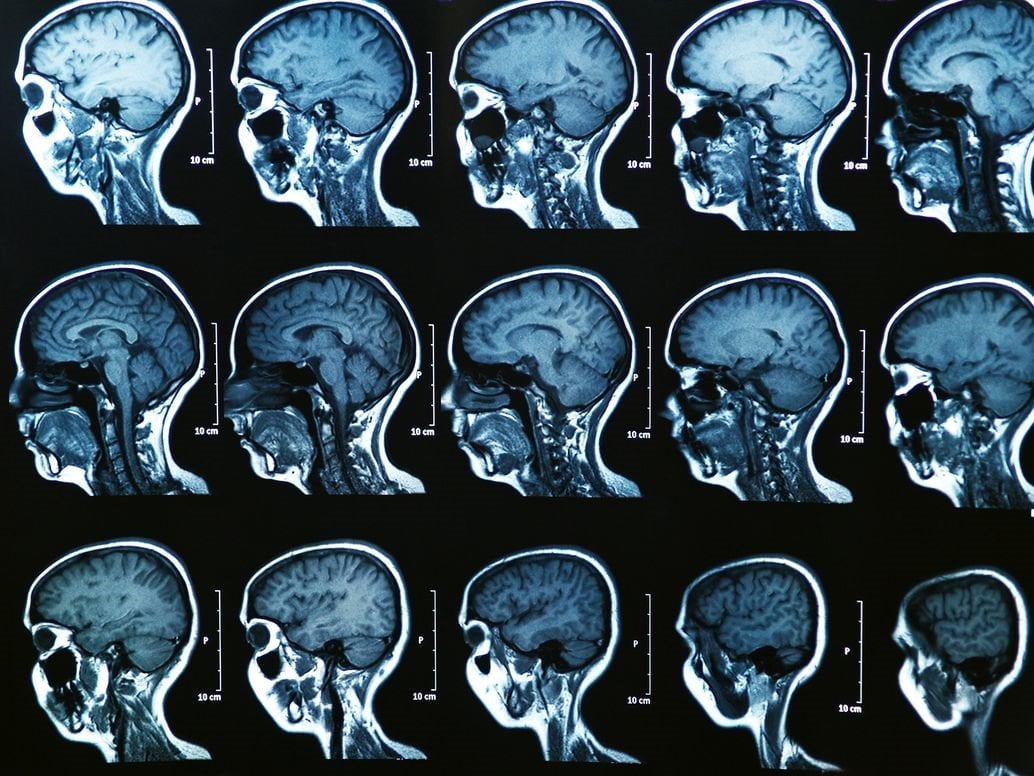

Jednym z najbezpieczniejszych i najbardziej dokładnych badań obrazowych, pozwalających ocenić struktury układu nerwowego oraz mózgu jest rezonans magnetyczny głowy. Pozwala on nie tylko na postawienie odpowiedniej diagnozy, ale również monitorowanie skuteczności wdrożonego leczenia, w tym również leczenia operacyjnego. Warto wiedzieć jak się do niego przygotować i jakie są wskazania do jego wykonania.

Rezonans magnetyczny głowy to nowoczesne badanie obrazowe, które wykorzystuje unikalny wpływ pola elektromagnetycznego na ludzkie komórki. Pod wpływem wysyłanych przez aparaturę impulsów, jądra atomów w komórkach zaczynają emitować fale, które są odbierane przez specjalne detektory i za pomocą zaawansowanego oprogramowania przekształcane na szczegółowe obrazy. W ten sposób możliwe jest nie tylko zobrazowanie struktur kostnych, ale również tkanek miękkich, a także ocena funkcjonalności poszczególnych narządów.

Co pozwala zobrazować rezonans magnetyczny głowy? Przede wszystkim struktury głębokie mózgu, w tym również istotę szarą korową oraz istotę białą. Dzięki temu badaniu możliwe jest także dokonanie oceny wewnątrzczaszkowych odcinków nerwów czaszkowych, a także mostu oraz rdzenia przedłużonego. Rezonans magnetyczny głowy jest badaniem wielopłaszczyznowym, dlatego też pozwala zobrazować m.in. płaty skroniowe, przysadkę, pień mózgu oraz ciało modzelowate.

Doskonale nadaje się również do oceny naczyń wewnątrzczaszkowych, a także tętnic szyjnych i zatok jamistych. Dzięki temu możliwe jest również wykrycie ewentualnych konfliktów naczyniowo-nerwowych. Jak widać możliwości diagnostyczne rezonansu magnetycznego głowy są szerokie, co uzasadnia jego częste wykorzystanie w rutynowej diagnostyce.